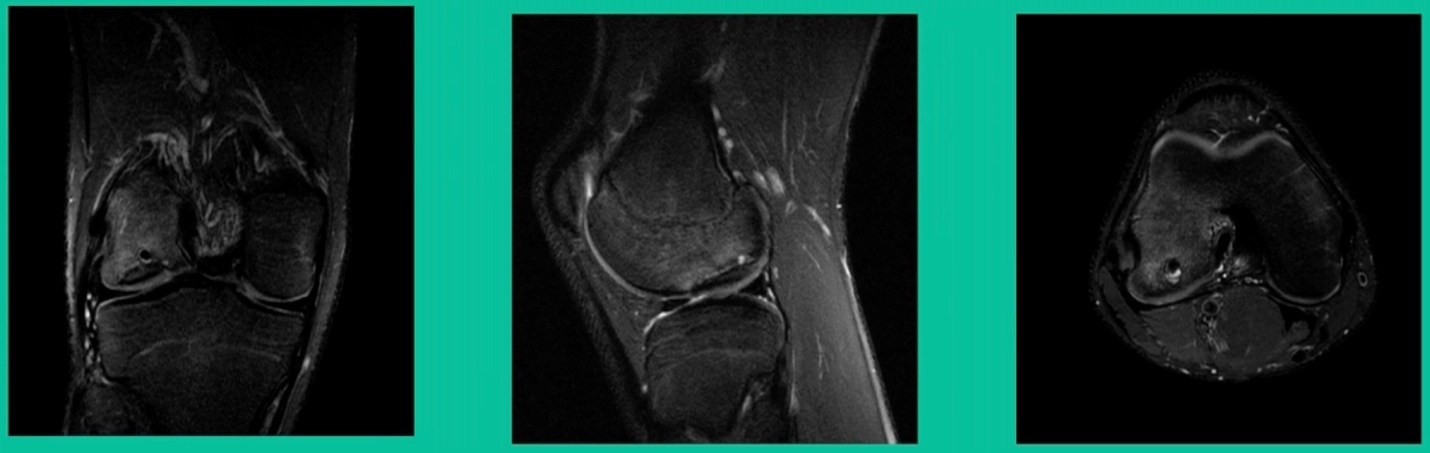

This is an 18-year-old with a lateral femoral condyle OCD:

Worsening over the last two years, has effusions but no locking, and has a large area of involvement that appears unstable. This is the classic fixation. If you can do this, this is the holy grail. Remember, fracture non-union: you elevate it, debride the base, get rid of any unstable fragments, just take them out, and preserve the major fragment. I’ll use a microfracture awl, but most commonly now I’ll use a pick or a pin, and I’ll drill it. I use two to three metal screws. I bury their heads, and then I come back at eight weeks after being non-weight-bearing, and pull the screws out.

Afterwards, I’ll allow them to fully weight-bear, wait eight more weeks, and then they go back to full sports. How do these do? Amazing. If you can get this to heal in an adult, this should last hopefully forever. The results over here show 80 to 90 percent healing rates in most series.